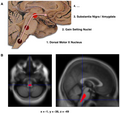

Features:[53]

- Abnormally pale substantia nigra.

- Pigmentation increases with age.

- Pale locus ceruleus.

Notes:

- Substantia nigra is a midbrain structure.

- Image: Midbrain - schematic (WC).